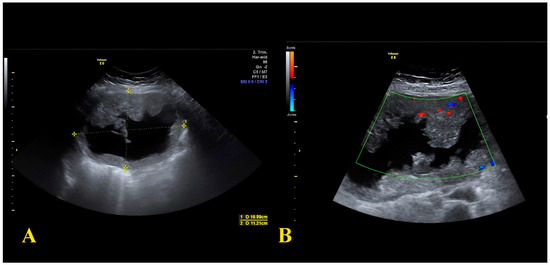

2.2. Case Report 2